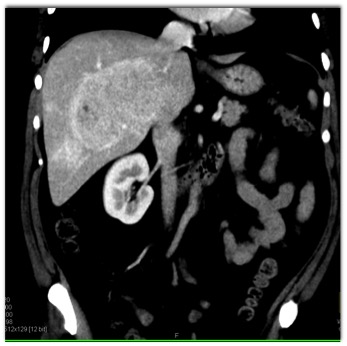

In this 30ish year old female with abdominal pain the most likely diagnosis is?

CTisus Quiz   CTisus Quiz

hemangioma

hepatoma

focal nodular hyperplasia

hepatic adenoma